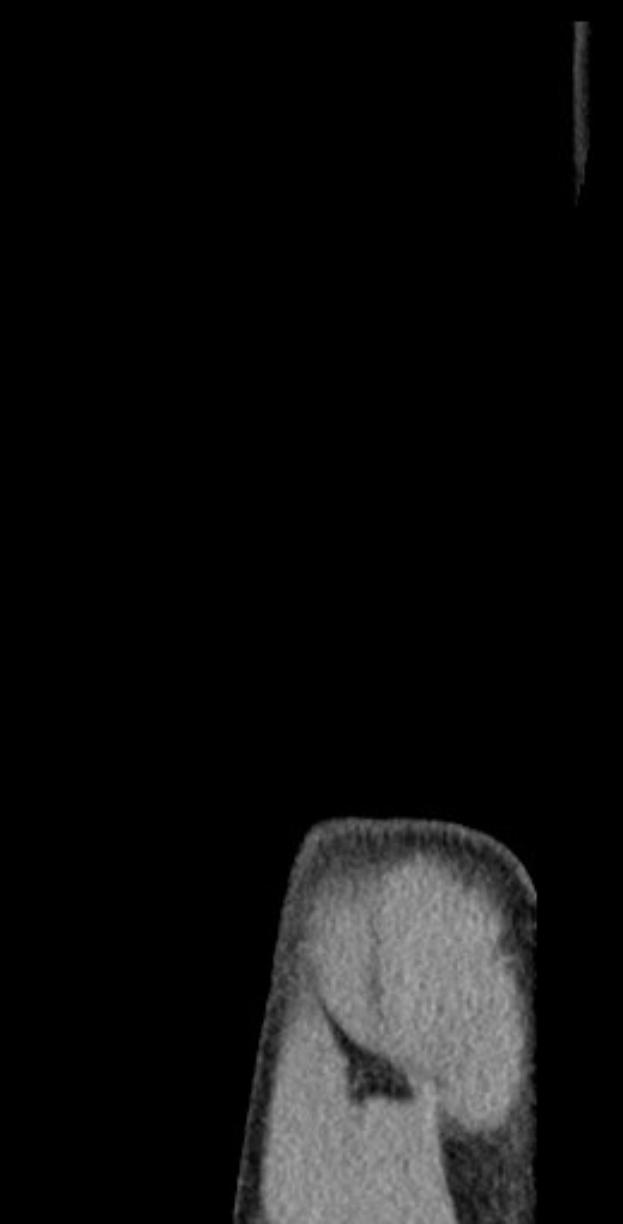

Hertha-BSC-Verteidiger Linus Gechter erleidet einen weiteren Rückschlag: Beim U21-EM-Qualifikationsspiel Deutschlands gegen Griechenland musste er mit Schulterschmerzen das Feld verlassen. Der 21-Jährige, der in der vergangenen Saison bereits acht Monate wegen einer ähnlichen Verletzung pausieren musste, wird nun einer MRT-Untersuchung unterzogen, um das Ausmaß der Schädigung zu klären. Sein Verein zeigt sich unsicher über die Schwere des Problems.